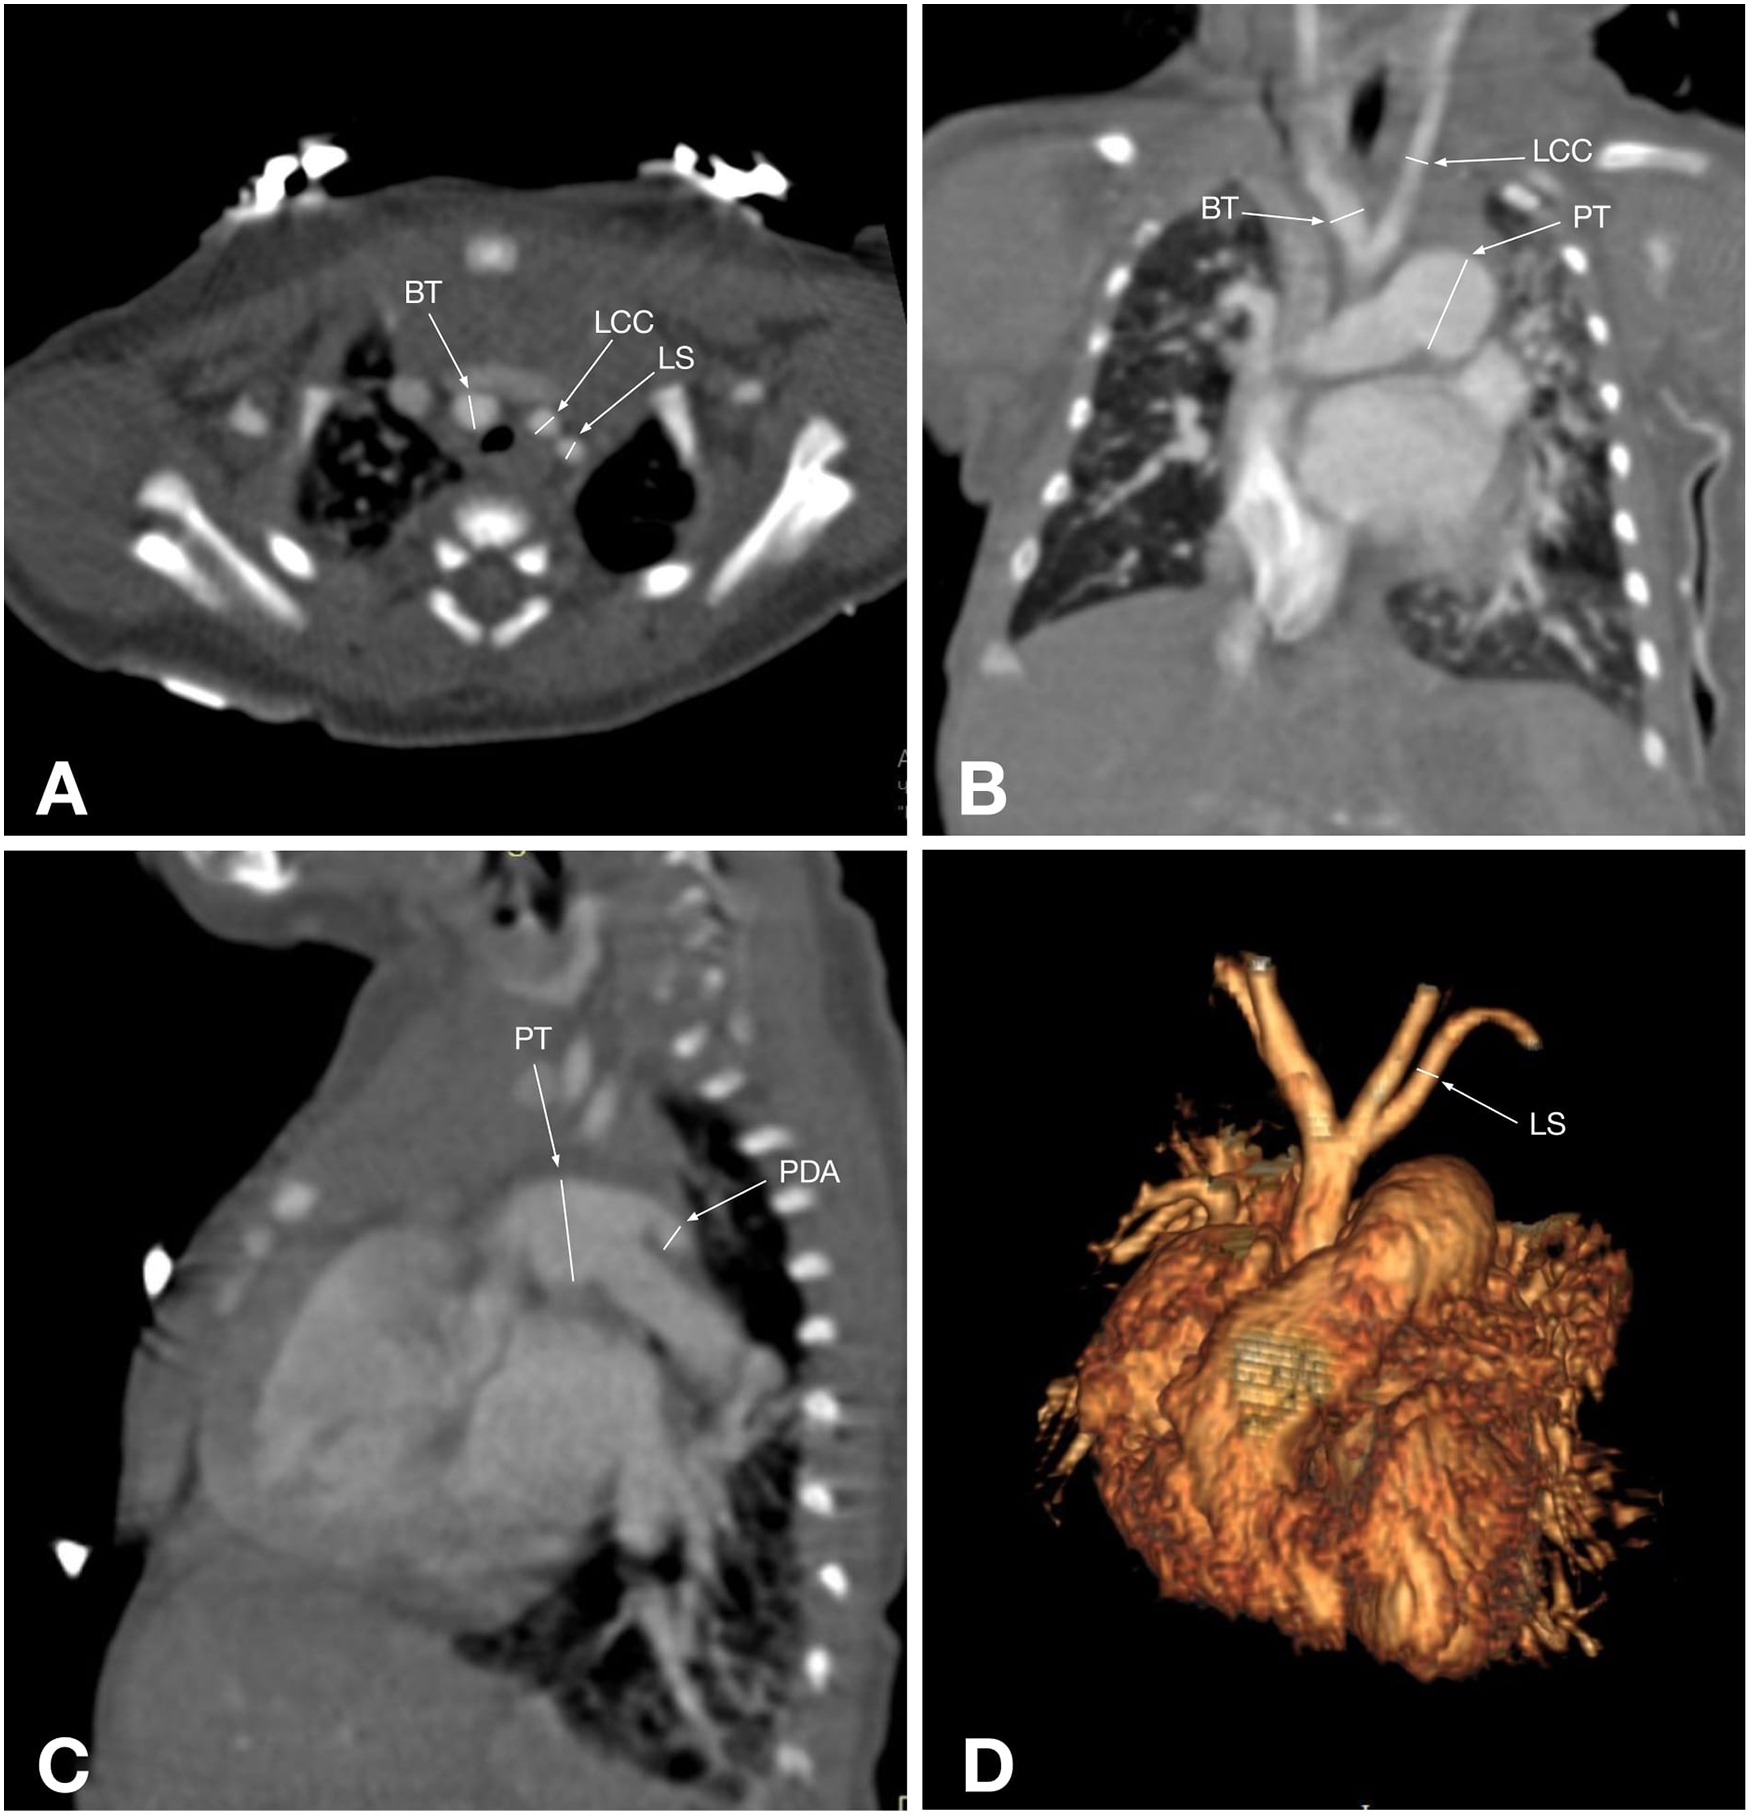

CTA provides a detailed visualization of AA anatomy and its spatial relationships with adjacent organs. Its advantage is further enhanced by various post-processing techniques, such as volume rendering, maximum intensity projection, and multiplanar reformatting, which can be applied to all structures within the scanned volume, making it superior to other imaging modalities for evaluating AA anomalies (5) (Figures 2, 3). Also, CTA is widely utilized for proper treatment and follow-up, as well as for preventing morbidities and mortalities (40). Traditionally, CT scans have been associated with high radiation exposure; however, recent advancements in radiation dose reduction technologies have significantly lowered the levels of exposure (41).

Figure 3. CT angiographic multiplanar images of a 55-day-old patient with type A IAA: (A) axial plane shows the branches of the aortic arch: brachiocephalic trunk (BT), left common carotid artery (LCC), and left subclavian artery (LS); (B) coronal plane shows that the ascending aorta branches into the brachiocephalic trunk (BT), which gives rise to the right common carotid artery. Also, the left common carotid artery (LCC) arising separately from the ascending aorta, the enlarged pulmonary trunk (PT), and its right branch are visualized; (C) Sagittal plane shows the pulmonary trunk (PT) continuing into the descending aorta via the patent ductus arteriosus (PDA); (D) 3D reconstruction shows an interrupted aortic arch after the left subclavian artery (LS) arises, corresponding to type A aortic arch interruption.